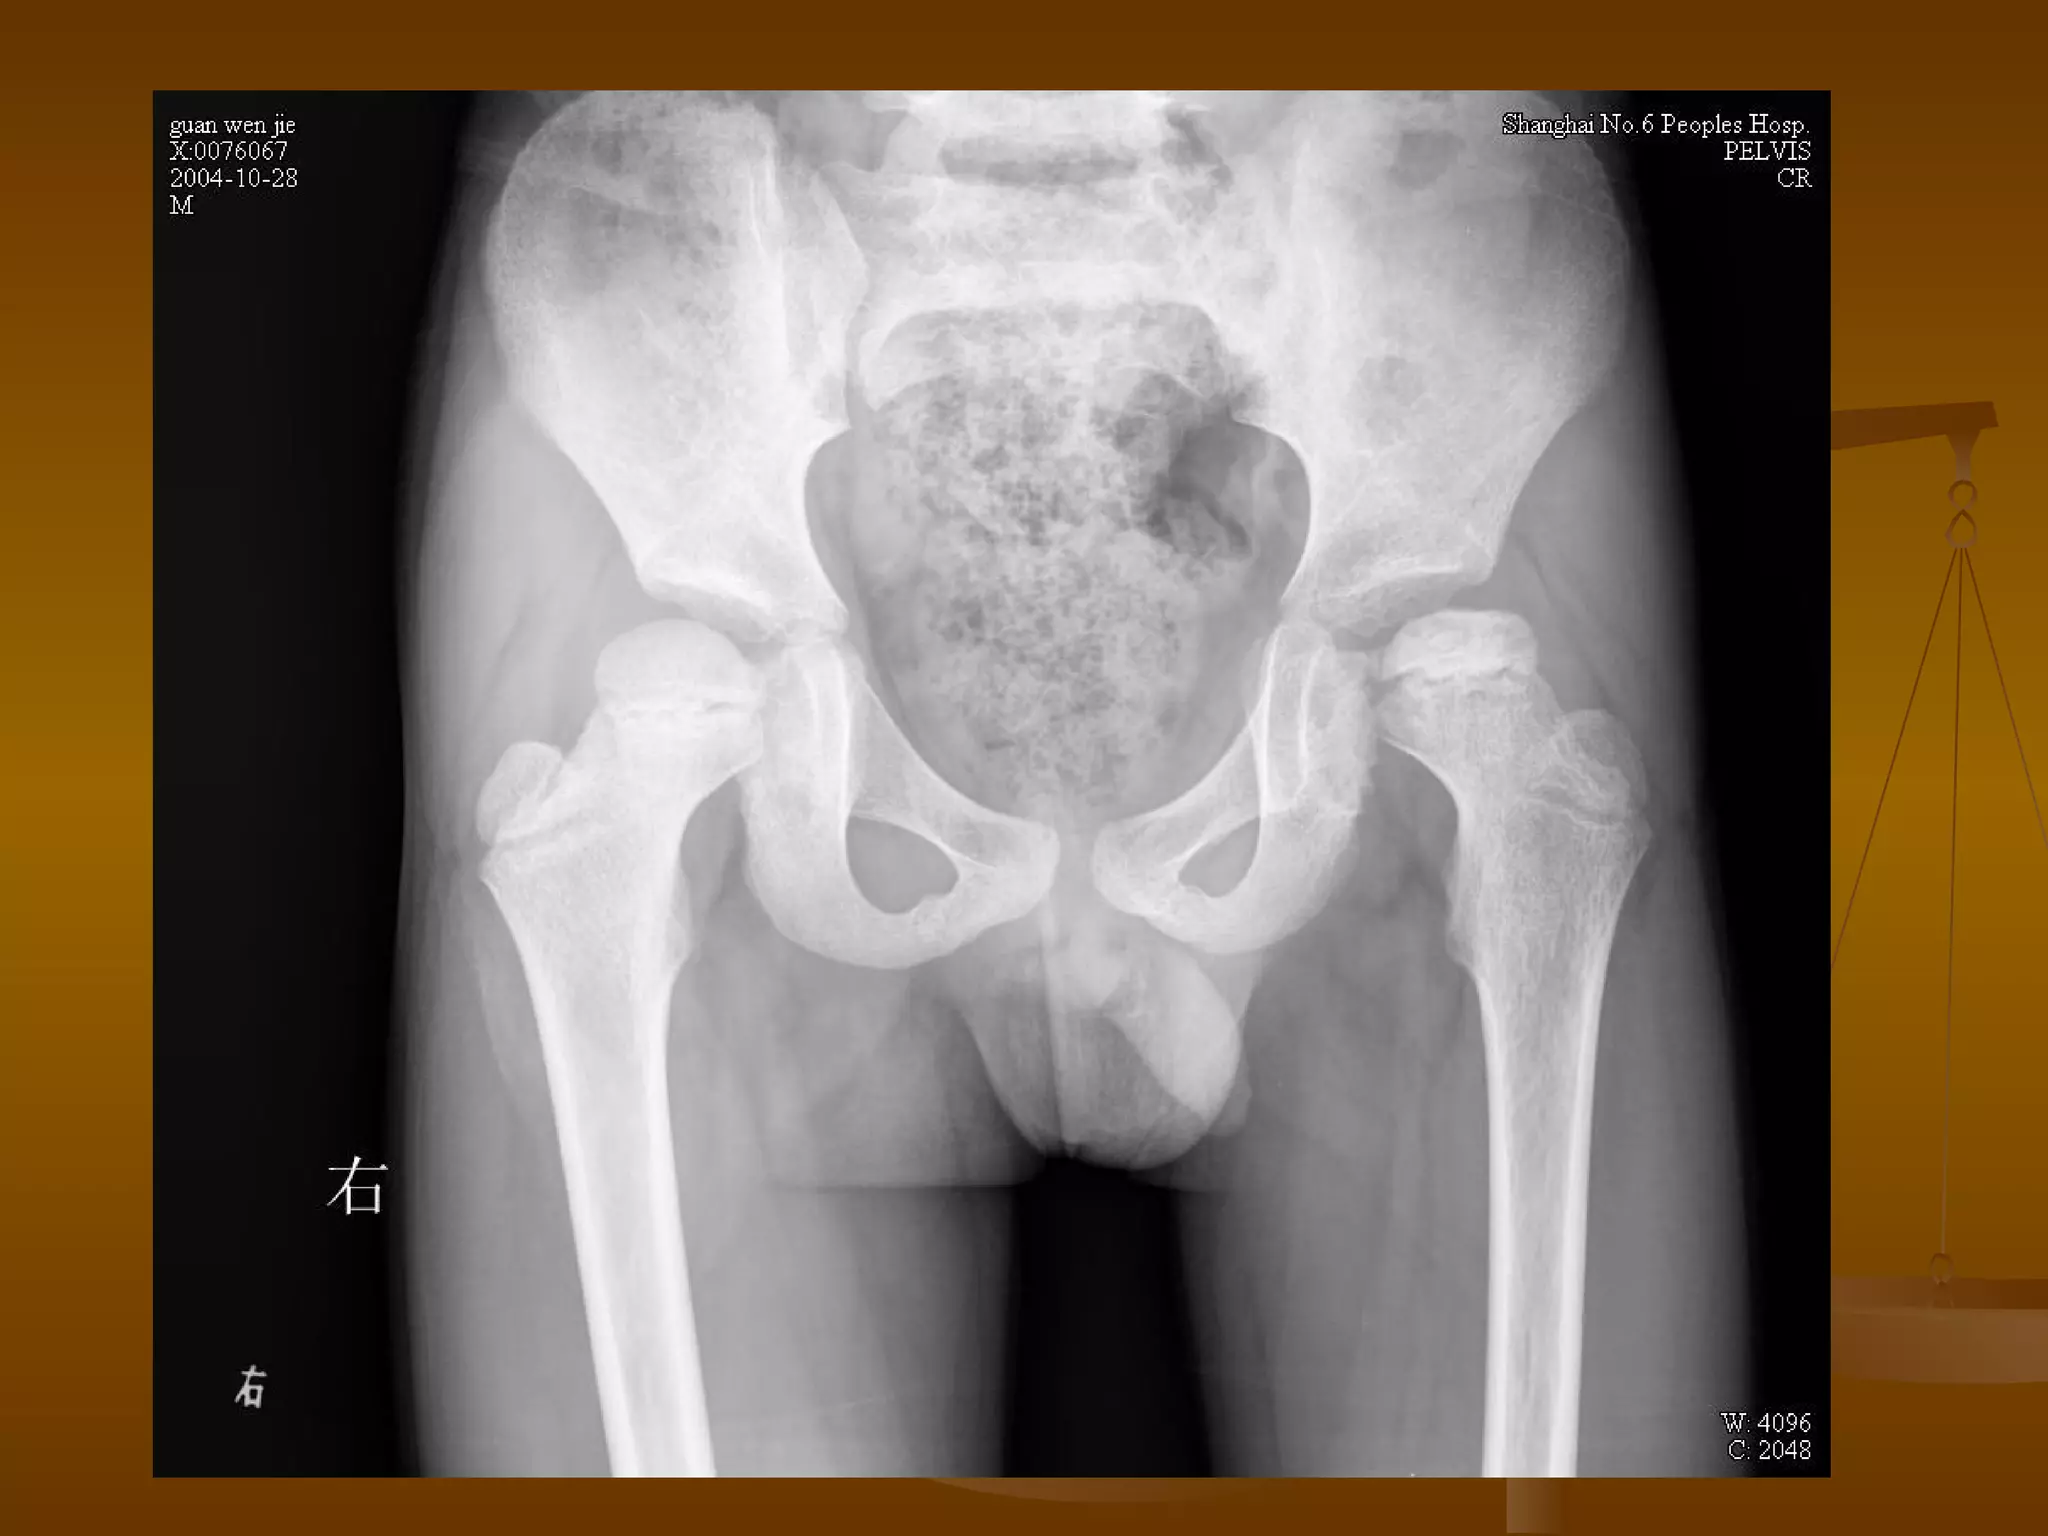

X 线诊断 X 光表现—晚期 股骨头明显变形、压缩、塌陷、骨密度不均匀。 病灶可累及整个股骨头,最终出现股头分节、碎裂。 并导致髋关节间隙狭窄和退行性骨关节炎。

CT 诊断   Ⅳ 期 股骨头增大变形、碎裂。 股骨头内骨质密度不均匀,累及整个股骨头,可见股骨头骨折。 关节间隙狭窄。 髋臼关节面受累,广泛增生、硬化、囊变,髋臼增宽变形。 盂唇骨化,出现退行骨关节炎。

MRI 诊断   Ⅳ期 关节软骨彻底破坏,髋关节间隙狭窄,合并关节退行性改变。 髋臼面软骨下骨质可出现囊性变,髋臼缘骨赘增生。 股骨头因骨坏死、囊变、骨折而显著塌陷、变形,受累范围可局限于股骨头上部或累及整个股骨头。 股骨头出现分节碎裂、骨折移位。